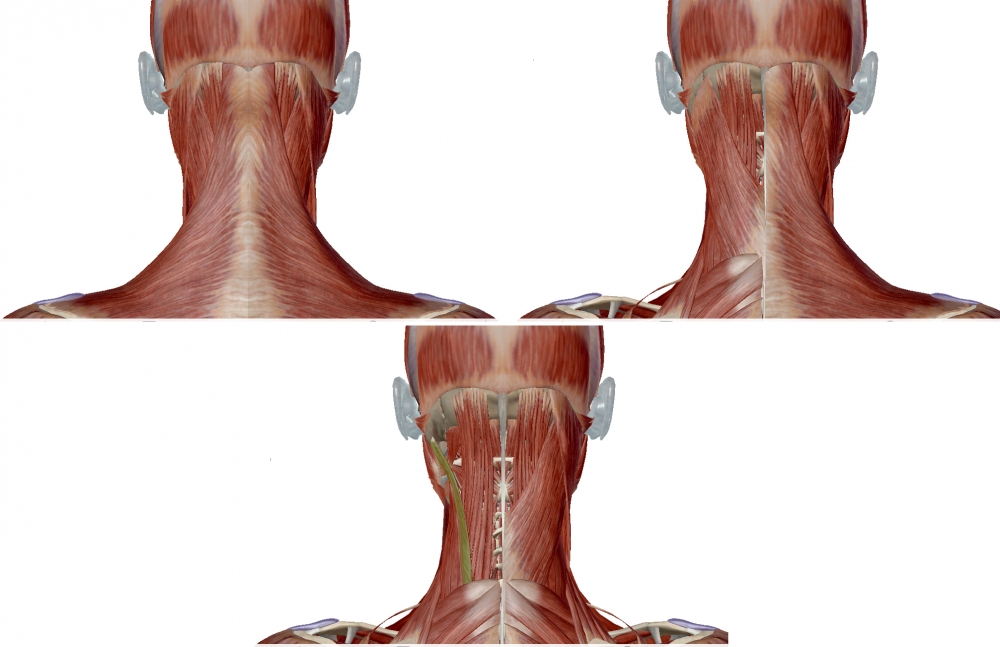

LONGISSIMUS CAPITIS LONGISSIMUS CERVICIS RECTUS CAPITIS POSTERIOR MAJOR SEMISPINALIS CERVICIS SEMISPINALIS CAPITIS

Origin: posterior surface of transverse processes of T1 to T6

Insertion: posterior margin of mastoid process and the temporal bone. The insertion is deep to that of the sternocleidomastoid and splenius muscles.

Action: Acting bilaterally, extends and hyperextends head

Acting unilaterally, flexes and rotates the head ipsilaterall (ipsiversion). The rotation is ipsilateral, and rotation of the head takes place at the atlanto-axial joint.

From: Mezaki T. Ultrasoundâ€guided botulinum toxin therapy for deep muscles in cervical dystonia. Neurol Clin Neurosci 2020; 8: 3–10.

Note that in the figure on the right, splenius capitis is transparent, allowing for the longissimus capitis to be seen deep to splenius.

The longissimus capitis lies between the longissimus cervicis (which is directly lateral to it) and the splenius capitis (which is directly medial to it).